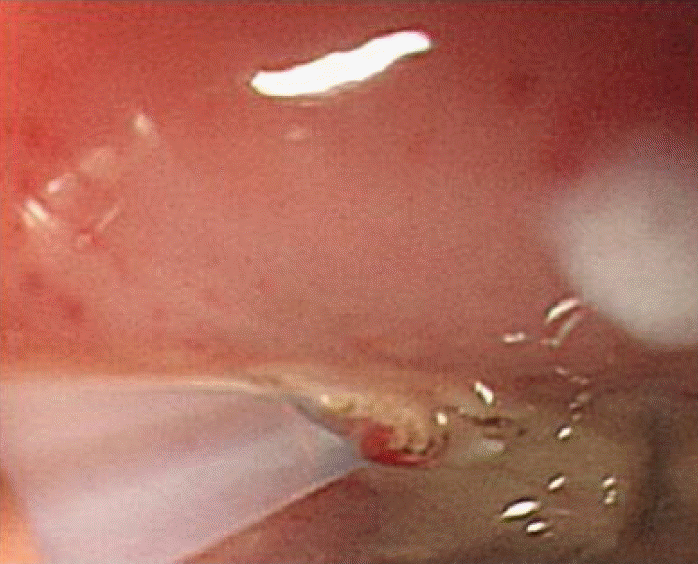

Figure 5.

Endoscopic finding showing drainage of the periesophageal abscess by a polytetrafluoroethylene introducer tube.